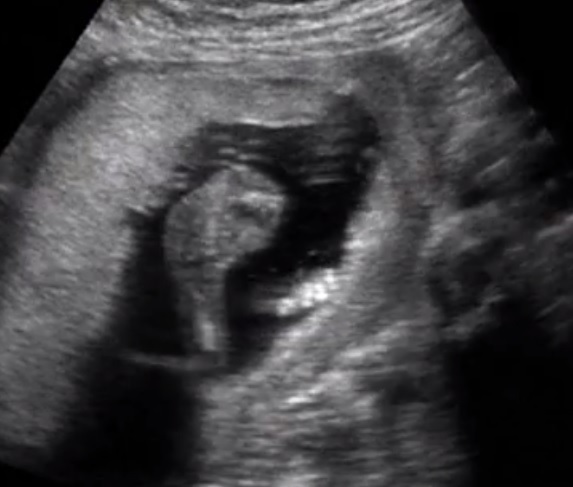

Pretty sure this is your boy!! Espescially the 6th pic from the bottom I see a very clear turtle which I have seen 3 times in my life before ;)

Boy from the 6th pic. FX for you!!